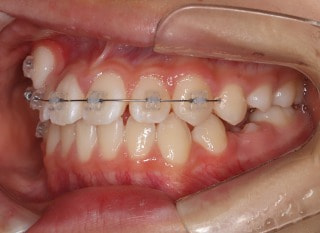

前歯装置装着時

小児期第一段階

終了時